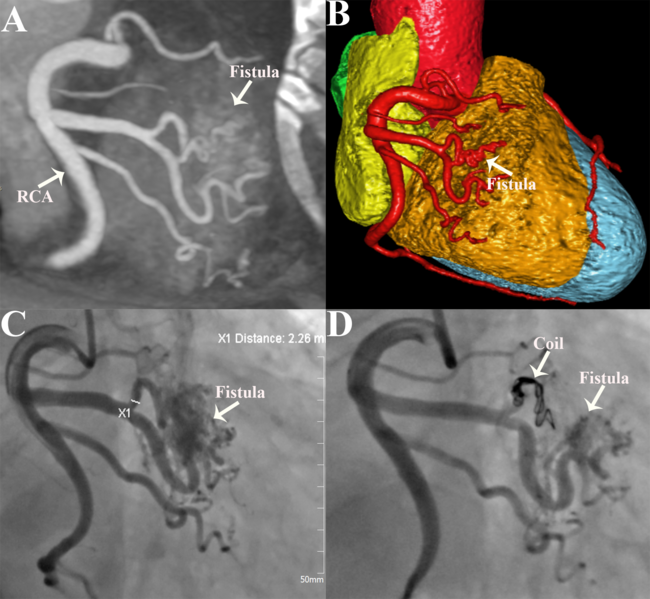

A 65-year-old man presented with intermittent chest tightness and shortness of breath for 8 months. The physical examination and laboratory tests were unremarkable. The electrocardiogram revealed sinus rhythm and inverted T-waves in leads II, III, and aVF. Transthoracic echocardiography showed an enlarged left heart and mild left ventricular hypodiastolic dysfunction. Coronary computed tomography angiography (CCTA) showed multiple microfistula between the multiple branches of the right coronary artery (RCA) and right ventricle (Figures A and B). Coronary angiography (CAG) demonstrated coronary artery-right ventricular multiple microfistulas (CA-RVMMFs) arising from the branches of the RCA (Figure C, Video 1).

The patient was treated by embolizing a large fistula vessel with an interlock coil (Fibered IDC; Boston Scientific) measuring 5 mm x 15 cm. Postoperative color Doppler flow imaging and CAG images revealed that the coronary fistula had been successfully embolized and the amount of shunting was significantly decreased (Figure D, Video 2). The postoperative course was uneventful, and the patient was discharged after 3 days. At the 6-month follow‑up, the patient's symptoms were significantly relieved.

Congenital CA-RVMMFs are rare anomalies, and the clinical and hemodynamic sequelae are incompletely understood.1 They result from the failure of obliteration of intertrabecular embryonic sinusoids and may cause angina pain or myocardial ischemia through the coronary steal mechanism.2 The characteristics of CA-RVMMFs during selective CAG are the visualization of small vessels interposed between the epicardial coronary vessels and the heart cavity.3 The optimal management of CA-RVMMFs is controversial, with no established guidelines. Options include percutaneous intervention, particularly in symptomatic patients or those with existing myocardial ischemia. Our case highlights the crucial role of CCTA and CAG in the accurate diagnosis and guidance of clinical treatment.